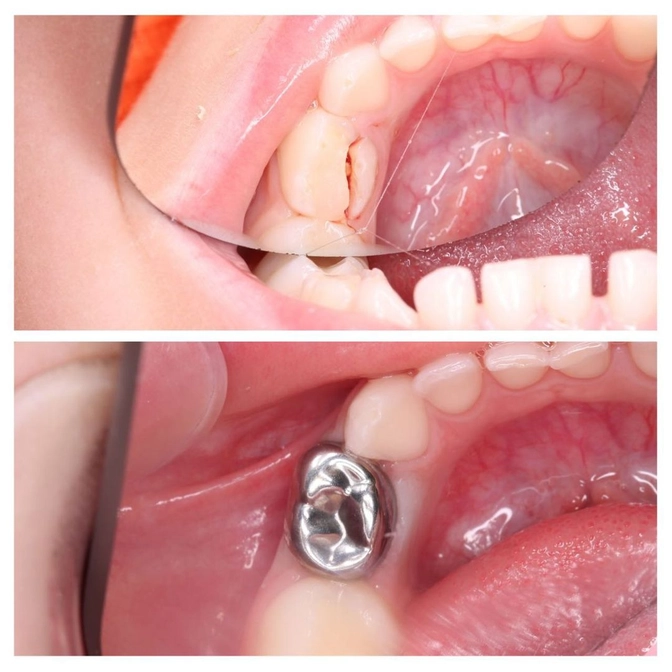

В 2019 году наш детский стоматолог Мария Штельмах лечила этот зуб по пульпиту.

В июле 2020-го она этот зуб поломала - это вы видите по фото.

И спустя время все получилось!

Обошлись аппликационной анестезией,

коронку все-таки зафиксировали.

Теперь зуб надежно защищен!

Коронка полностью и герметично закрывает весь зуб, не позволяя ему разрушаться.